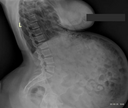

>>95664 Xrays like this easily done by photoshop. And any prop-maker can do stuff like that for ~$20 Also there's lot of mistakes - vertebra looks like "pure enlongated neck", in belly mostly looks like gases, but it's not eggs - hard boiled eggs on x-ray looks like black yolks and white whites , and here's some plastic shit. Also some square objects, or gut bendings. Eggs looking like 2-3cm, but "large" is 5-6cm And her "belly reports" seems like she holded first 100 eggs for 1 day without digesting, and 200 more added for 2 days in a row and h0olded all 300 eggs in stomach without digesting for 4 days - 100 eggs can be digested for 1 day, ask Molly Shuyler - she ate 100 eggs with shells once and 112 eggs mostly without chewing for 8 minutes 2nd time. Her photos 50/50 morphed or she using extra pads under clotches. Maybe even she uses "fake pregnant belly" prop. On one of her Patreon early photos seen stretch marks on belly, but I'm not sure about it. She also has too slim body to that belly - even Bloatedbellybabe more fat everywhere exept neck.

Like serous talk (i follow a lot of comp eaters and stuffers) and i suspect voraisha can genuinely eat a lot. She seems to be doing this full time now given her sub count and patreon count which means if she's really trying for this shes doing stomach exercises and then working out to keep fat down and stretching her stomach out (water/electrolyte mixes and fibre like watermelon and veggies and similar) to low cal train her body to eat and keep her weight down (otherwise fat blocks the stomach from expanding, essentially). This may explain why she has a weird streaming schedule sometimes. Now, on whats she's eating i can't say for sure but compared to competitive eaters shes a lightweight. The biggest meal recorded by a comp eater was 30kg over 4 hours - notorious BoB at an eating challenge in the US. That's all on tape with mediators so no fakery, but a key note is that he focused mainly on liquid foods where possiblle because your body can process it quicker. Comp eaters similarly are eating ridiculous amounts in tiny time periods, for instance 10kg of grits in 10 minutes, or 71 hotdogs (~8kg) in the same. So voraisha eating 10kg in a 2-3 hour stream isn't actually that unreasonable, but what i suspect is happening is she (from listening to audio) is washing down food a lot with water or soda to bloat herself, particularly when you can hear her actively chugging like a litre at a time. Normally comp eaters are drinking a little bit to moisten food and make it easier to swallow and churn, not to fill them selves up. Famously some literally dip everything in their water cup. So 80kg of food was probably actually 50kg of food plus fluid. 300 eggs maybe was 300 eggs, but that's only ~15kg of eggs if theyre on the small side, and again pretty possible from known records, especially if it was over 2-3 days, and again epecially with fluids to help stuff move. Now the queation i have is that if these feats are are legitimate and not embellished... Why not film it? Why not enter competition level eating? Why only so photoshoots the week after when you would of passed a lot of it and actively comment you can bloat yourself out with water when you want now? The only conclusion i can draw is that she is embellishing somewhat and therefore has to rely partially on fakery to keep things interesting. A new record belly size isn't gonna keep subs up if it isn't actually a new record. The xray is fairly clearly bogus though, ive seen x-rays of comp eaters who had issues and they look nothing like that. The stomach is a j shape and when expanded straightens out somewhat (this is the health risk - it csn straighten up and crush your liver and pancreas ans why there is medical reports on comp eating risks) Honestly as said i have an open mind on this, I think ahe can eat and stuff herself well, but k suspect she is embellishing it a bit now. If she did a full video of it or belly shots during id retract all this but as its just audio and before/after it makes it impossible to confirm it.

>>98847 Same thoughts I heard from Google Gemini when I tried to analyze her stuff through that AI. Same thoughts had I after discovering about real stuffers e.t.c. SO. Her "stomach" is fake: on very first Patreon photos it's not so big - she possible drank 2-3l of water or just sticking out her belly to look it "bloated". Later she asks in one Patreon post about if she will use "fake vore belly". Later her early posts about that deadly challenges with tons of food & water for 1 stream she shows clumsy edited photos, her bellybutton on naked belly looks unnatural. Later looks like she uses pads like pillow or maybe even "pregnant stomach" prop, that used in motion pictures. Shape of her "belly" under allways lot of clotches is same. Size too. That x-ray (that she calls "body screen") fake as hell. Her sounds with that tons of reverb is just a "radio-show". I sure she actually never eats that much and she can't swallow even small chicken egg, but she told about that 300 eggs was "large", not extra-jumbo, but not small and not even medium. She once shown her "naked belly" not so long time ago - >>96882 - and looks like it's just a damn knee from POV. On X she posted "super cozy digestion" photo and it more looks like empty chair orr pillow under that plaid... I totally not believe in any her content. Maybe very-first photos iss legit, maybe gummy videos is legit, but it's not a big deal and other is completely fake, cuz no one competitive eater, even Molly Shuyler, can't go in her rhytm - it will be deadly even for Molly, even for legendary Tarrare, even for... I dunno... Human body can't do that anyway.